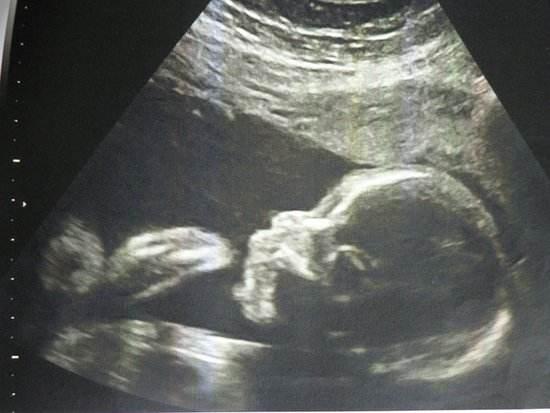

早期肝硬化通过B超通常可以检查出来哦!肝硬化说白了就是慢性肝病发展的结果,肝脏会慢慢变硬、出现纤维化。B超检查特别有意思,它就像给肝脏做"超声波透视",通过回声图像能清楚看到肝脏大小、形态变化。早期肝硬化虽然症状不明显,但B超已经能捕捉到肝脏回声增粗、表面不光滑这些蛛丝马迹啦!

影像学检查更直观:除了B超,CT和MRI这些高大上的检查能立体呈现肝脏形态。肝硬化中期以后,肝脏会缩小、表面变得坑坑洼洼,这些变化在影像下一目了然。弹性成像技术更是黑科技,直接测量肝脏硬度值,超准的!